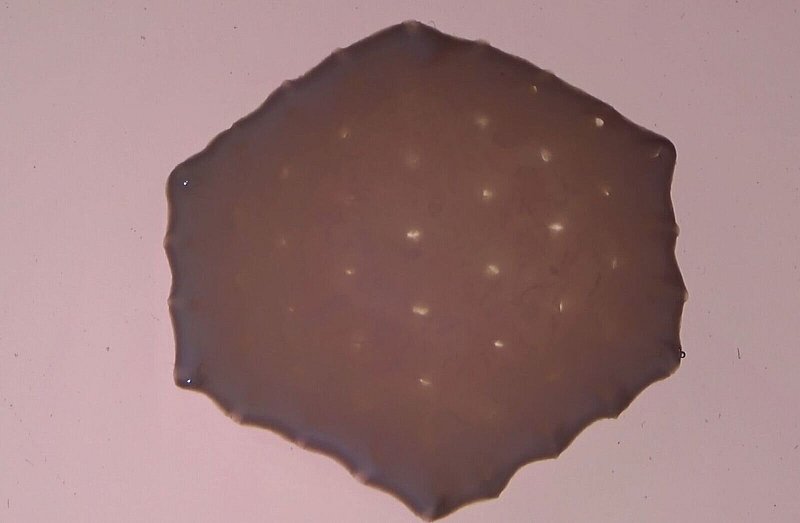

Im Labor gezüchtetes Herzmuskelgewebe

Für das «Herzpflaster» wird aus den iPS-Zellen Herzmuskelgewebe gezüchtet, das sowohl Herzmuskelzellen enthält als auch Bindegewebszellen. Die Herstellung dauert laut Zimmermann etwa drei Monate. Das aus mehreren Teilen zusammengesetzte und nach Forscherangaben etwa 100 Kubikzentimeter große Implantat wird auf den geschwächten Herzmuskel aufgebracht und soll die Pumpleistung dauerhaft erhöhen.